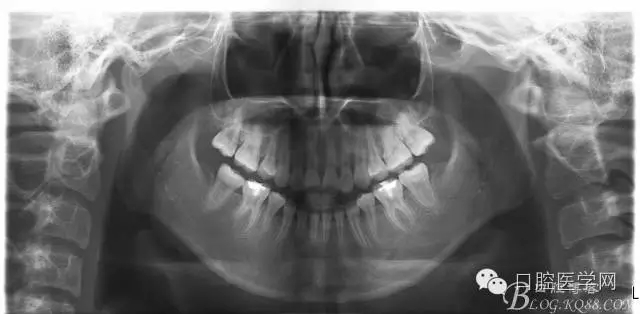

正畸查:替牙合。第一恒磨牙中性合。上牙弓尖圓型下牙弓方圓型。前牙覆合3度覆蓋7.5mm。下前牙咬到上舌側(cè)牙齦。上頜擁擠4.0mm,下頜擁擠

3.0mm。上頜稍前突下頜后縮,上下唇前突,上前牙覆蓋下唇,下唇外翻。面下三分之一過(guò)短,頦唇溝明顯,開(kāi)唇露齒,頦饜窩明顯。顳下頜關(guān)節(jié)開(kāi)閉口無(wú)彈響,無(wú)壓痛,開(kāi)口型開(kāi)口度正常。

設(shè)計(jì):

1:SWA.

2:拔牙矯治,拔出4顆第一前磨牙。

3:上下頜利用拔牙間隙解除擁擠并內(nèi)收上下前牙,改善唇側(cè)貌。

4:導(dǎo)下頜向前改善頜面?zhèn)让病?/p>

5:上頜TPA+NanceArch強(qiáng)支抗.

6:下頜囊腫開(kāi)窗引流,雙側(cè)第一恒磨牙舌桿保持牙位。擇期拔除第一前磨牙。